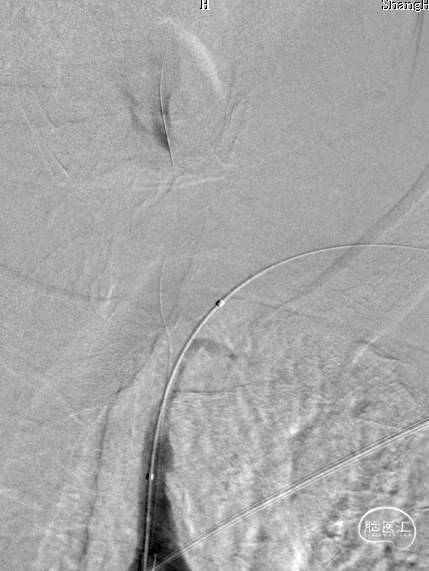

造影见LV闭塞,立即沿0.014*200cm 通桥北斗SS™神经血管导丝置入3mm*16mm 药物球扩支架至LV1。

压力泵逐渐加压球扩支架到8atm, 支架打开良好,造影示残余狭窄0%。

双侧锁骨下动脉造影见椎动脉、基底动脉血流通畅,远端未见栓塞表现。

术后头晕呕吐,当日DWI:左侧小脑梗死,MRA未见明显大血管栓塞。

术后第3天患者恶心、呕吐症状消失,仍有头晕,复查DWI及MRA。

术后第5天,头晕症状完全消失,双上肢收缩压差8mmHg,NIHSS 0分。